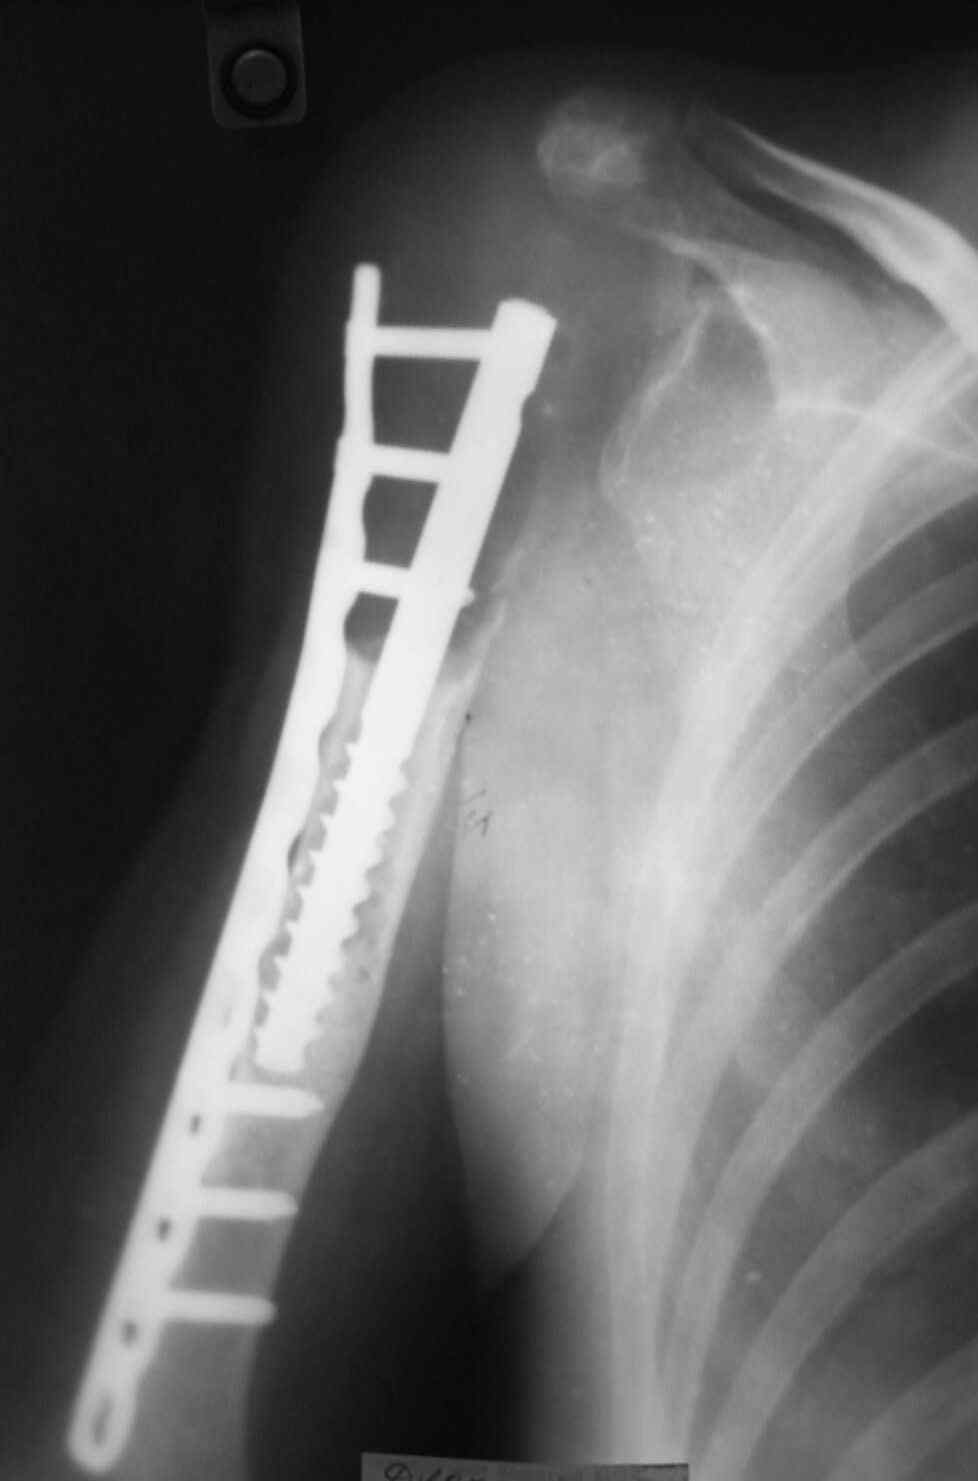

14 лет назад больной имлапнтирован протез плечевой кости выполненый по методике Воронцова на штифте-штопоре Сиваша,за 2 года до имлапнатации в онкологическом учереждении больной выполнена резекция проксимальоной части плечевой кости по поводу ОБК, ксенотрансплантации головки, и последующем его удалением на фоне гнойного процесса. У больной имелся втянутый обширный рубец и болтающееся плечо, афункциональная верхняя конечность, выраженный косметический дефект.П/опрационный период без осложнений, сохранялась выраженная контрактура в плечевом суставе, но стаилизация плеча и косметический эффект больную устраивал,даллее контакт с больной был утерян ( поменяла место жителсьтва. Через 14 лет полноценной жизни сельской жешщины ,больная нашла нас с клиникой выраженной нестабильности протеза. Категорически отказалась от замены протеза.

Выполнена операция- малоинвазивно проведена LCP пластина в образованный канал над головкой протеза, фиксирована к протезу и дистально к плечевой кости, на зоной резорбции трепонирована кость, удалена соединительно-тканная оболочка, полость заполнена chronOS. П/о период без осложнений, клиника нестабильность купирована.Прошло 2 года по телефону сообщила, что у нее все хорошо, продолжает жить счастливой жизнью сельской труженицы

Головка отлита из акрилоксида( то чем мы располагали в прошлом веке), он полность Р-прозрачен, по методике Воронцова рекомендовалось добавлять Р-контрастные добавки,например сульфат бария, учитывая, что он давал раковины в полимере, мы это не сделали.Кстати, довольно крепкий получился, затупили 2 сверла.